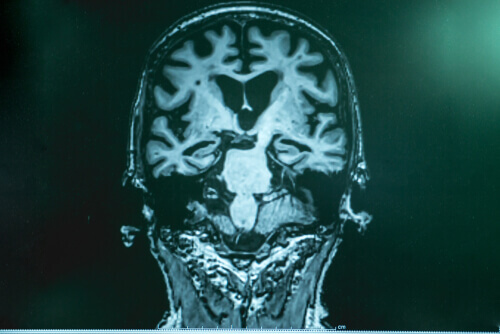

Dr. Lopera legt uit dat er bij de ziekte van Alzheimer een soort ophoping van ‘afval’ in de hersenen is. Het bestaat uit een eiwit dat amyloïde wordt genoemd.

Fragmenten blijven aan elkaar plakken en vormen vervolgens een soort ‘lijm’ die aan de neuronen blijft plakken en een aantal storingen in de hersenen veroorzaakt. Het andere deel van het ‘afval’ is tau, dat zich om het neuron wikkelt, het opsluit en het tot slot doodt. Tau is schadelijker.

Na zorgvuldige studies in Boston ontdekten experts dat de hersenen van de patiënt gevuld waren met amyloïde, zelfs met meer dan in andere gevallen. Ze had echter heel weinig tau. Het onderzoek stelde hen in staat om te verifiëren dat bij deze specifieke patiënt een andere mutatie de productie van tau remde en dit was wat de voortgang van de ziekte vertraagde.